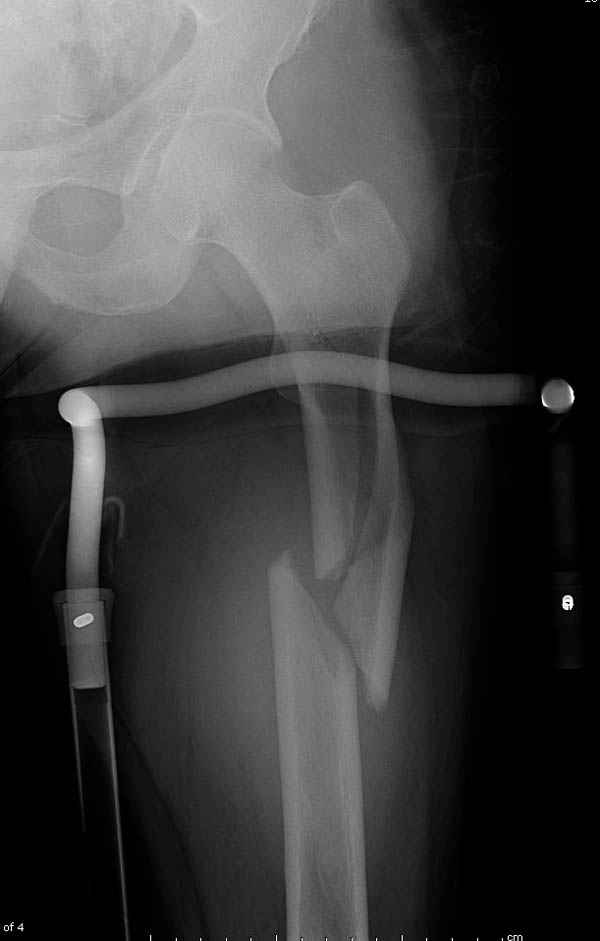

Среди русскоговорящих коллег Ортофорум стал одним из мест, где многие из нас черпают знания для решения своих ежедневных проблем в виде практических советов и обмена опытом. Кроме таких советов, Ортофорум стал источником новых познаний среди ортопедов, особенно по редко встречающимся состояниям в ортопедии. Продолжая традицию, я хотел бы представить редко встречающий случай перелома бедра у больного с гемофилией. Больному 42, гемофилия типа А, из истории упал с высоты около 1,5 метра, переправлен из другой больницы. По происхождению мексиканец, 10 лет назад по поводу артроза пр. коленного сустава в Мексике сделано протезирование, которое закончилось ампутацией выше коленного сустава. При поступлении бедро напряженное, сосудистых и неврологических расстройств нет. На рентгенограмме оскольчатый перелом бедра с вовлечением проксимальной спирали в шейку бедра. Хотели бы знать тактику ведения подобных больных и на что надо обратить внимание? Djoldas Kuldjanov, MD Department of Orthopedic Surgery St. Louis University Medical Center

Учитывая, что случай ургентный, больной поступил вечером, не стали делать вытяжение и срочно провели операцию по фиксации перелома бедра антеградным штифтом Versa Nail от DePuy.

Для профилактики дальнейшего раскола в шейке предварительно во время проксимального рассверливания спереди и сзади провели временные спицы, которые в дальнейшем были заменены на шурупы (miss nail method)

Обычная спасательная фасциотомия для обычного больного в этом случае было бы приговором, поэтому несмотря на высокие цифры компартментального мониторинга больного оставили под наблюдением с обкладкой конечности льдом.

Кровотечение удалось контролировать, и больной через пару дней выписан на амбулаторное лечение.